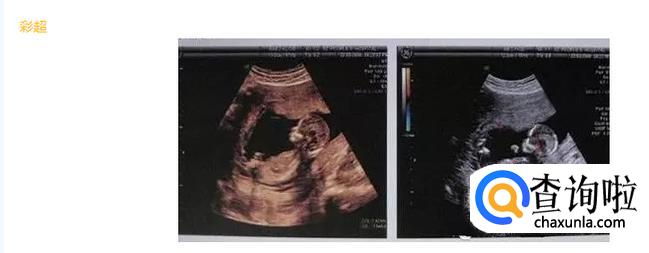

- 02

彩超并不是你们所想的字面意义上理解的“彩色的B超”,只是在普通B超的基础上出现了彩色多普勒超声波探测诊断技术。彩超其实还是黑白的,被称为彩超,是因为会用彩色标注心脏、血流等指标。彩超的分辨率会比一般B超高一些,所以在需要做比较细致的检查的时候,更多的医生愿意通过彩超来检查。彩超可以检测出宝宝内脏的情况以及有脐带绕颈的情况。